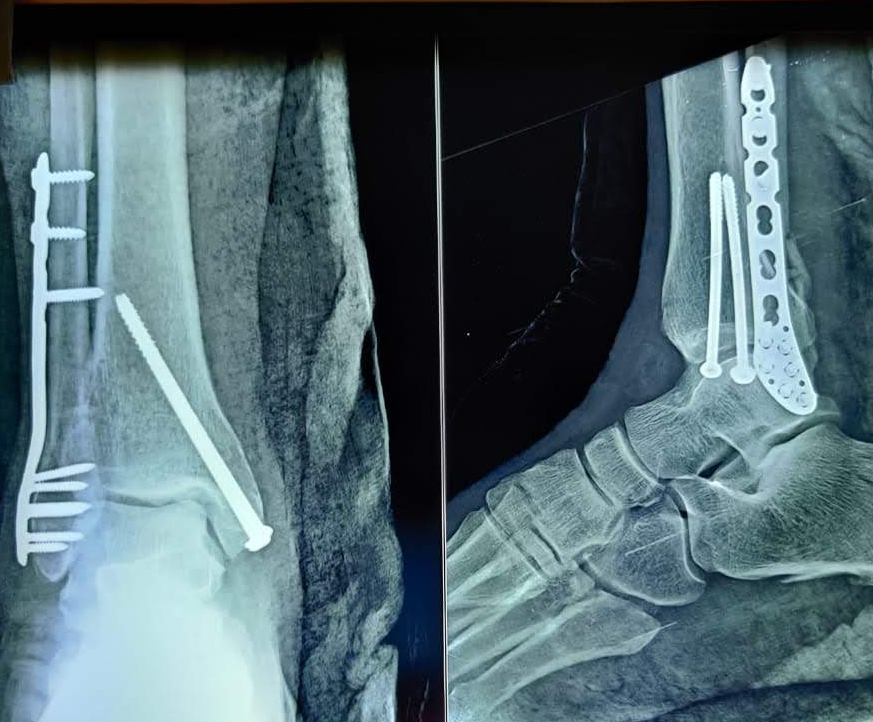

PROFILE TRAINING AND PRESENTATION Dr. Niranjanan Recieving Diploma SICOT degree in Rome, Italy Dr. Niranjanan being awarded fellowship certificate at Indian spinal injuries centre CLIINIC SOME OF Dr. NIRANJANAN's CASES